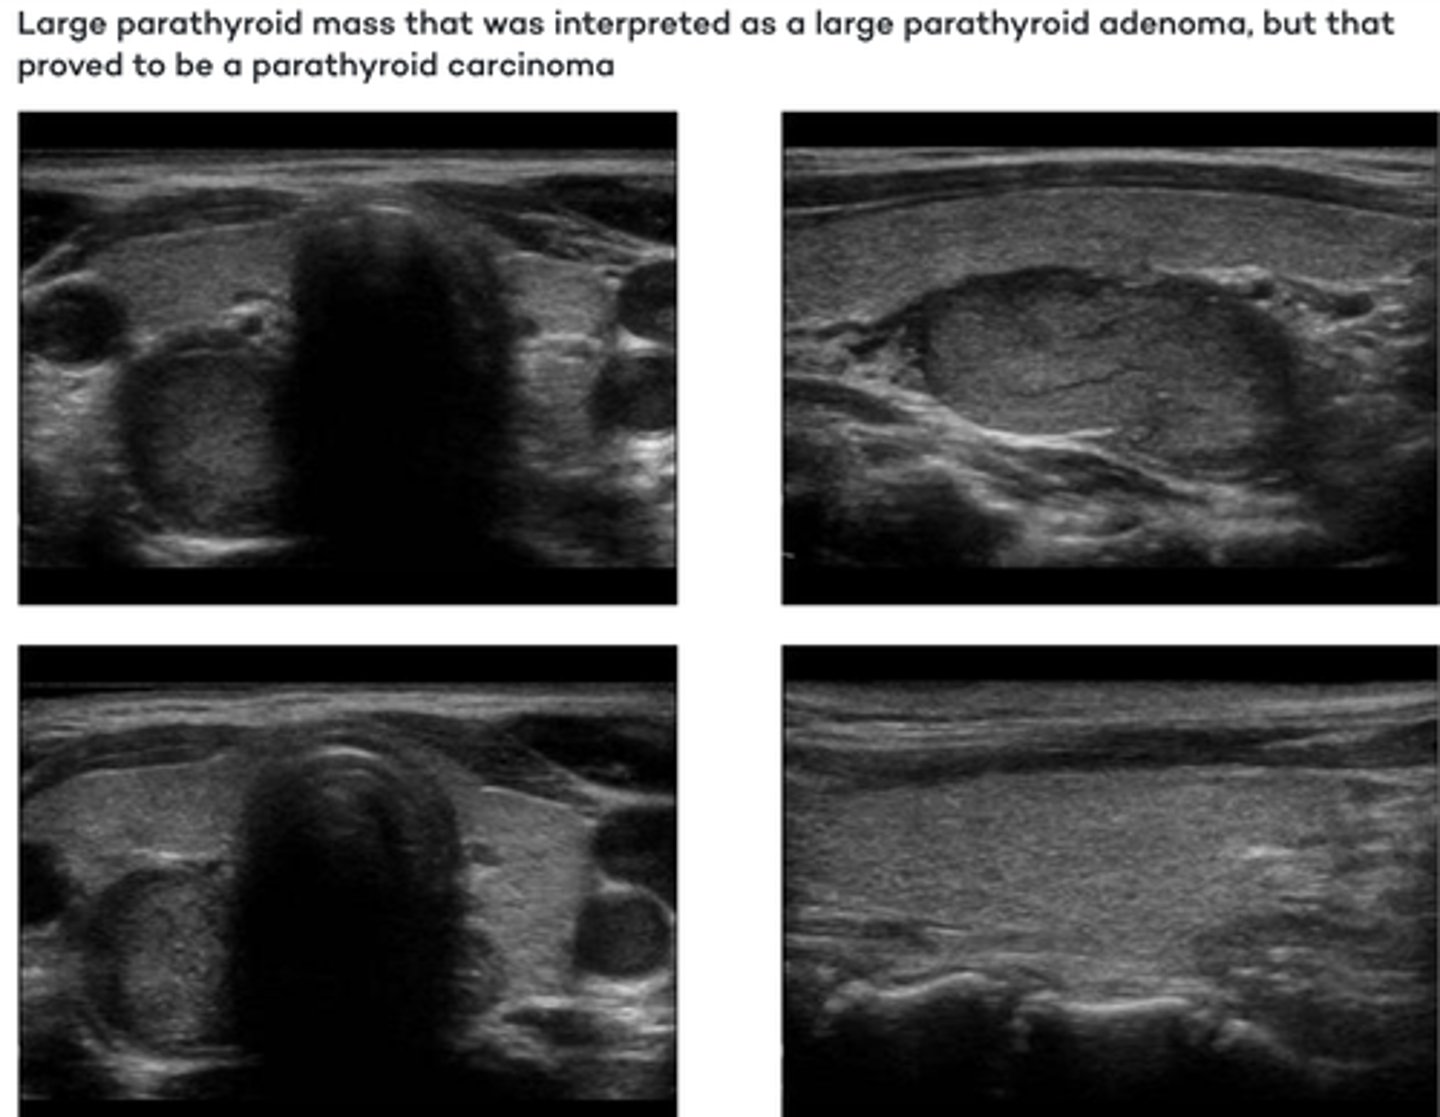

Parathyroid Pathology - Carcinoma:

Etiology

-_____ neoplasm

-_____-growing

-Tend to _____ surrounding tissues

Clinical findings

-_____

-Elevated _____ level

-_____ palpable neck mass

Sonographic findings

-_____echoic _____ mass

-Round or oval in shape

-_____ of sound (dense)

-_____vascular

-Epithelial neoplasm

-Slow-growing

-Tend to infiltrate surrounding tissues

-Hypercalcemia

-Elevated parathormone level

-Firm palpable neck mass

-Hypoechoic lobulated mass

-Attenuation of sound (dense)

-Hypervascular